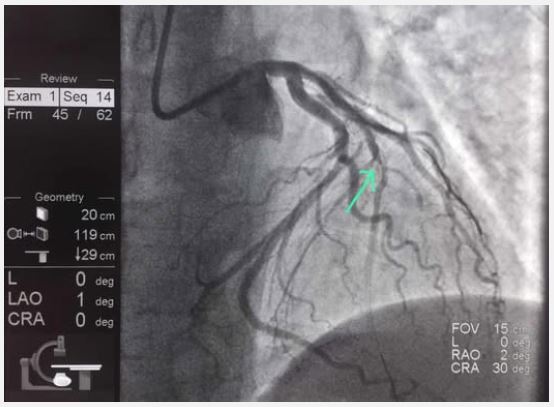

Nine days later, after consuming marijuana again, the patient presented with unstable angina. Clinical evaluation revealed normal bilateral vesicular breath sounds, a soft, painless abdomen, and no edema. Troponin level was 0.15 ng/ml (normal <0.06), ECG revealed ST-segment elevations in V2-V6 (Figure 2), and echocardiography showed apical akinesia, indicative of transmural MI. Coronary angiography revealed neoatherosclerosis with an unstable plaque and mural thrombus in the mid-segment of Left Anterior Descending (LAD) artery (Figure 3). Primary PCI was performed.

Figure 3: Coronary angiography showing neoatherosclerosis with an unstable plaque and mural thrombus in the mid-segment of the Left Anterior Descending (LAD) artery (Green arrow).